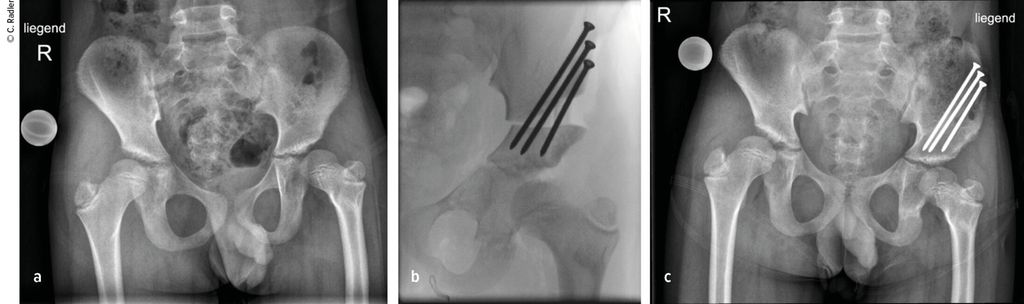

Im Rahmen dieser Operation können auch die Retrotorsion und der Schenkelhalsvarus korrigiert werden. Eine Verlängerung bei nicht optimal überdachter Hüfte führt meist zu einer Subluxation oder Luxation, was eine schwerwiegende Komplikation darstellt, die nur schwer und meist nicht folgenlos zu beheben ist. Auch bei älteren Patienten ist die Überdachung vor einer eventuellen Verlängerung zu überprüfen, wobei besonders ab dem 4. Lebensjahr eine Tripelosteotomie eine bessere Überdachung und Einstellung der Pfanne gegenüber einer Acetabuloplastik erlaubt (Abb.2).

Abb. 2:Versorgung eines kurzen Pfannendachs mittels Tripelosteotomie, um die Hüfte während der Verlängerung vor (Sub-)Luxation zu schützen